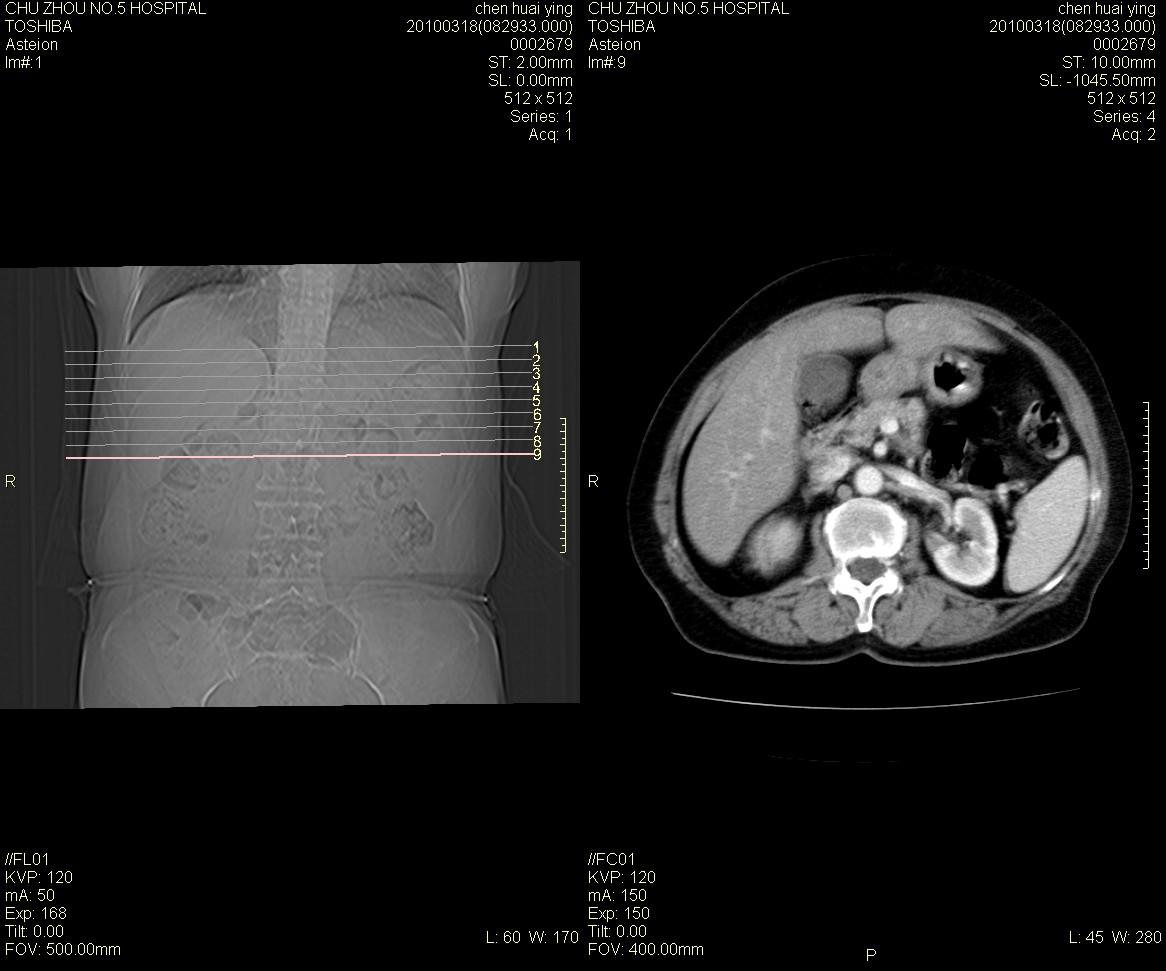

标题: CT25148 肾上腺增强

ct25148增强图片

动脉期太早了,扫的有点低。考虑良性占位右侧肾上腺嗜铬细胞瘤并坏死囊变可能性大,神经鞘瘤不排除。

右侧肾上腺占位性病变,病人是否有高血压?嗜铬细胞瘤?

右侧肾上腺嗜铬细胞瘤并坏死囊变可能性大

考虑双侧肾上腺肿瘤性病变。